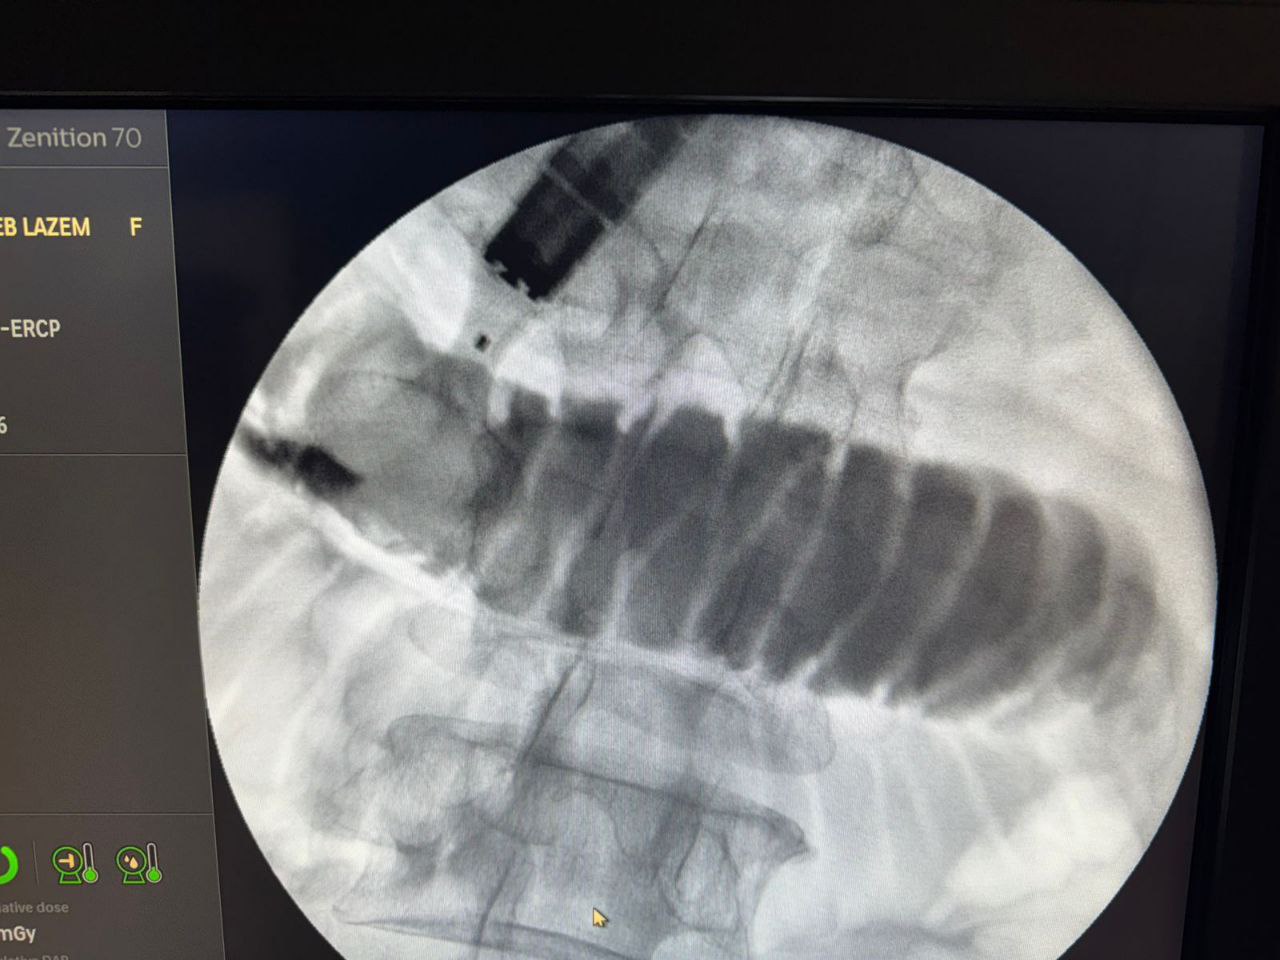

وقال رئيس هيئة الصحة والتعليم الطبي في العتبة الحسينية المقدسة الدكتور "حيدر حمزة العابدي" في تصريخ خص به وكالة نون الخبرية ان " هذه العملية هي واحدة من العمليات التي اجراها الليلة الدكتور "خالد رجب" في مركز الجهاز الهضمي بمؤسسة وارث الدولية وهي لا تجرى الا في المراكز المتقدمة في العالم، اما في العراق فلا يتم اجراءها اطلاقا"، مشيرا الى ان " العملية هي تحويل مجرى الطعام من المعدة الى الامعاء الدقيقة

من دون عملية جراحية وانما عبر ناظور الفم فقط، وتجرى للمرضى الذي يصبح لديهم انسداد في مخرج المعدة او الاثني عشري".